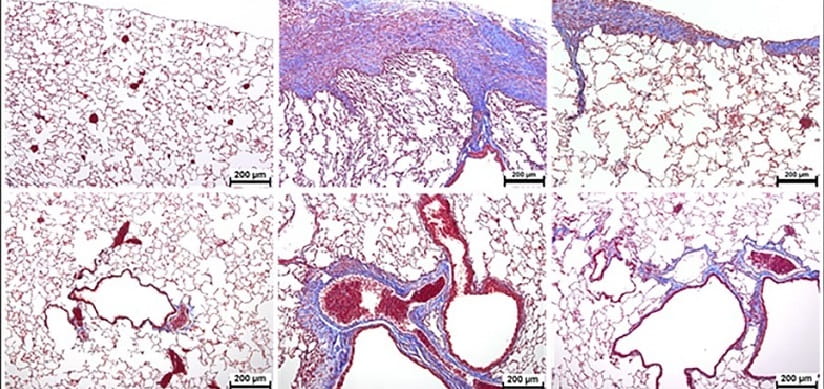

Inhibition of Aurora Kinase B attenuates fibroblast activation and pulmonary fibrosis. Kasam, RK; Ghandikota, S; Soundararajan, D; Reddy, GB; Huang, SK; Jegga, AG; Madala, SK. EMBO Molecular Medicine. 2020; 12(9):e12131.

Hsp90 regulation of fibroblast activation in pulmonary fibrosis. Sontake, V; Wang, Y; Kasam, RK; Sinner, D; Reddy, GB; Naren, AP; Mccormack, FX; White, ES; Jegga, AG; Madala, SK. JCI Insight. 2017; 2(4):e91454.